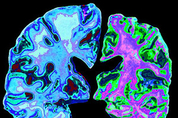

간단한 피부 생검(skin biopsy)으로 파킨슨병을 진단할 수 있다는 연구 결과가 나왔다. 파킨슨병은 운동을 조절하는 뇌 부위에서 분비되는 신경 전달 물질 도파민 생산 세포가 소실되면서 근육 경직, 몸 떨림, 느린 동작 같은 운동 장애가 나타나는 중추신경계 질환이다. 신경 신호 전달을 돕는 단백질 알파-시누클레인이 도파민을 만드는 신경세포에 쌓여 증상을 일으키는 것으로 알려져 있다. 미국 베스 이스라엘 디코니스(Beth Israel Deaconess) 메디컬센터 자율·말초신경 장애 실장 로이 프리먼 박사 연구팀은 파킨슨병의 주범으로 알려진 신경세포의 비정상 단백질 알파-시누클레인 응집을 간단한 피부 생검으로 확인할 수 있다는 연구 결과를 발표했다. 파킨슨병 뿐 아니라 루이소체 치매(DLB), 다계통 위축증(MSA), 순수 자율신경 부전(PAF) 등 알파 시누클레인 응집과 관련된 진행성 신경 퇴행 질환인 시누클레인병증(synucleinopathy) 모두를 피부 생검으로 진단할 수 있다고 연구팀은 밝혔다. 연구팀은 시누클레인병증 중 하나로 진단된 428명을 대상으로 목, 무릎, 발목 등 3개 부위의 피부 3mm를 채취, 생체검사를 진행했다. 그 결과 파킨슨병